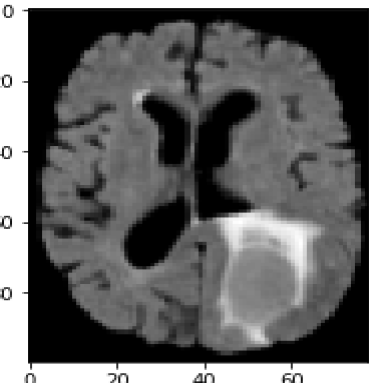

For the second medical example, we use image from the brain tumor segmentation (BRATS) challenge 2015 dataset; see https://www.smir.ch/BRATS/Start2015. The channels in this case consist of contrast-enhanced T1-weighted (T1c), T2 and fluid attenuated inversion recovery (FLAIR) images. Channels contain complementary information allowing accurate diagnosis and quantification of tumor growth. The top row in Fig. 7 shows the input images highlighting a different region of the tumor. Again, we exploit the information contained in different sequences by employing them as separate input channels. The proposed method is thus able to use this complementary information to delineate the different tissues and demonstrates solid results for this concrete example from medicine. The fact that the proposed energy functional can be applied directly to the given images, makes it particularly suitable for medical image segmentation.